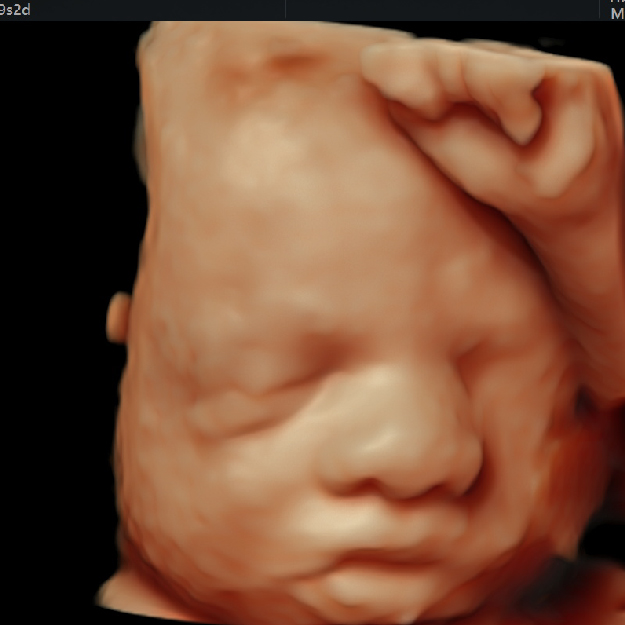

3. Confirmación de la vitalidad (latido cardíaco en el embrión/feto).

8. Evaluación anatómica del feto después de las 11 semanas (preferentemente 12-14 semanas).